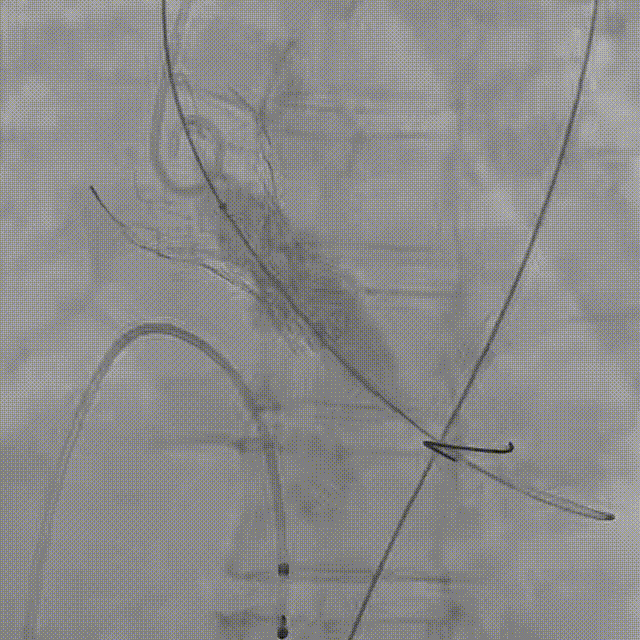

最终造影

患者病史 主诉:发作性胸闷憋喘半年,加重伴呼吸困难2周。 现病史:患者半年前无明显诱因出现胸闷、憋喘,伴有下肢水肿,2周前上述症状明显加重,夜间不能平卧,痰中带血丝,为进一步诊治再次来我院,门诊以"心力衰竭"收入院。 既往史:肾功能不全、心房颤动 心脏超声提示:LVEF:0.54 1.主动脉瓣病变;2.主动脉瓣狭窄(重度)并反流(中度);3左室壁节段性运动不良;4.升主动脉扩张、双房扩大、左室肥厚;5.二尖瓣硬化并反流(中度);6.三尖瓣反流(轻-中度);7.肺动脉瓣反流;8.肺动脉高压(轻度)PGmean=105mmHg,Vmax=635cm/s,瓣口面积0.27cm²。 术前CT评估 Type0型二叶瓣,重度钙化,钙化集中在瓣叶游离缘,右冠窦为著;左冠高度11.8mm,由于左冠窦部空间较小,左冠风险较高, 升主动脉扩张,最宽处50.5mm;主动脉瓣环水平夹角61.5°,横位心。主动脉弓角77.6°,锐角弓,外周入路在腹主及髂总处有大量散状钙化,胸主处有81.6°的迂曲。 手术策略 推荐右侧股动脉为主入路,左侧股动脉为辅入路,送snare辅助过弯,使用18F大鞘,推荐预装ProStyle A® AV23瓣膜,20mm球囊预扩,初始定位对齐真实瓣环瓣上5mm超高位初始定位释放,释放过程中使瓣膜自然下滑,到工作位观察瓣膜形态,最终理想位置0-瓣下3mm。 手术过程 Step1:右侧股动脉为主入路、左侧股动脉为辅入路,成功穿刺并送入 18F 大鞘; Step2:主动脉根部造影,瓣口限制重 Step3:Type 0 型二叶瓣畸形合并重度钙化,患者瓣口狭窄严重,同时横位心,不仅导丝跨瓣困难,导管更难进入;术者凭借精湛操作,将导丝顺利跨瓣,反复微调导管角度,最终导管顺利过瓣。 导丝精准跨瓣 Step4:20mm球囊跨瓣困难,snare辅助下球囊成功跨瓣,预扩有腰无漏,冠脉充盈良好。 Step5: snare辅助下成功跨瓣,可以看到系统过弓形态瓣膜仓柔软,过弓顺滑 输送系统过弓 Step6:初始定位瓣上5mm开始释放,释放部分后观察瓣架下缘内收明显,后回收系统重新定位 初始定位 底部内收 Step7:瓣膜完全释放前,血压一度降低,术者迅速调整器械,实现瓣膜迅速锚定,快速释放 完全释放 Step8:20mm球囊后扩 最终造影,位置(瓣下3mm)形态良好 手术难点 患者不仅有主动脉瓣重度狭窄,还叠加肾功能不全、心房颤动等基础疾病,术中血流动力学波动极易引发心功能衰竭。ProStyle A® 预装干瓣“开包即用” 的特性压缩了术者操作时间,80%可回收设计给了术者容错空间,而这些看似难以逾越的难关,最终被团队精湛的医术一一化解,术中对于导丝、导管、球囊等器械每一步的精准操控,再到突发状况的从容处置,无不彰显着团队深厚的专业积淀与顶尖的操作技艺。 结语 此次手术的圆满成功,不仅彰显了陈玉国、李传保教授团队在复杂结构性心脏病介入治疗领域深厚的专业造诣与攻坚克难的决心,也充分验证了ProStyle A®系统在应对复杂高难度病例时的卓越适用性与有效性。 作为扎根齐鲁、享誉全国的医疗高地,山东大学齐鲁医院始终赓续着这片热土的仁厚文脉,将“医道从德,术业求精”的院训精神镌刻在每一次诊疗实践之中。特别是在结构性心脏病诊疗领域,医院团队始终怀揣医者担当,勇攀医学高峰,不断以更前沿的技术突破,为危重患者点亮重获新生的希望。 专家简介 陈玉国 山东大学齐鲁医院(点击查看专家详细简历) 李传保 山东大学齐鲁医院(点击查看专家详细简历) · END ·